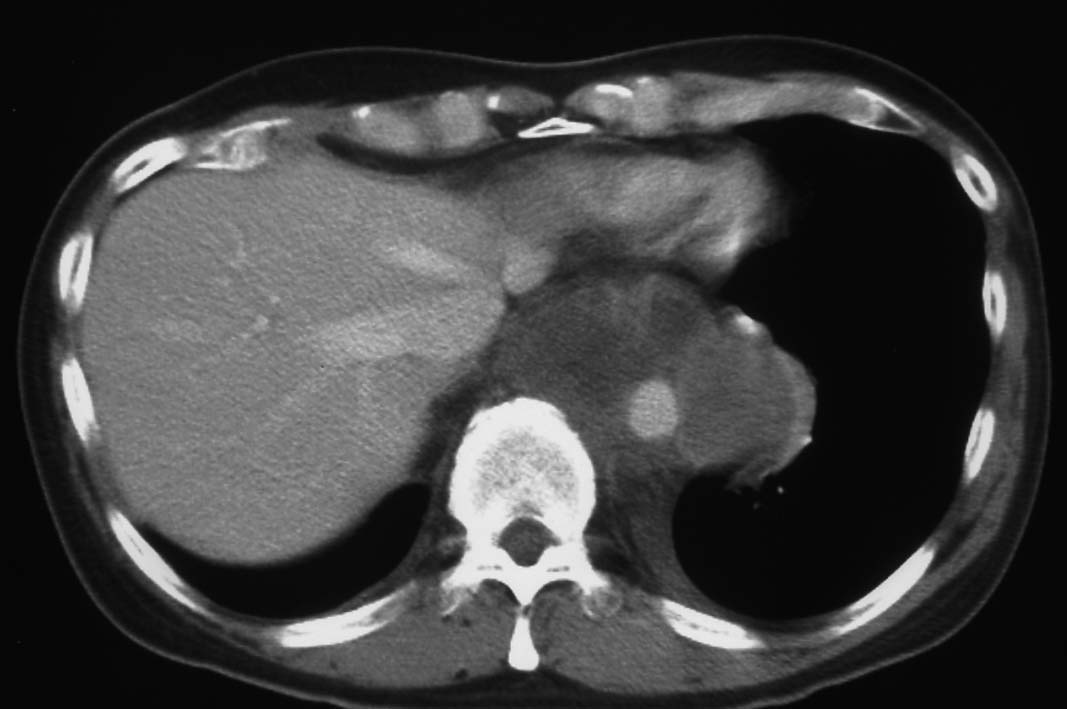

5ヵ月後右主気管支を圧迫しほとんど閉塞する巨大な腫瘍を認めた. 他院で緊急放射線療法および化学療法を行うが効果なし. 腫瘍切除+右肺上葉切除をおこない肉眼的には腫瘍は完全切除できた. 病理診断は非典型的であるが malignant SFT. 当院に再入院, radiation therapyをおこなう. 効果乏しく, 腫瘍は進行し呼吸不全で永眠される.

胸腔鏡下ブラ切除術5ヵ月後, 縦隔腫瘤で再発. 他院で腫瘍切除+右肺上葉切除を施行. 肉眼的には腫瘍は完全に切除できた.

初診から11ヵ月, 胸部つかえ感出現. CTで気管分岐部から横隔膜食道裂孔を通り, 腹腔内へ進展, 食道および大動脈を囲繞する巨大な腫瘍が再発した. 他院での抗がん剤感受性テストの結果より, CDDP+5FUによる化学療法がおこなわれたが効果乏しく全身状態悪化. 呼吸不全が進行し初診より約1年の経過で永眠された.